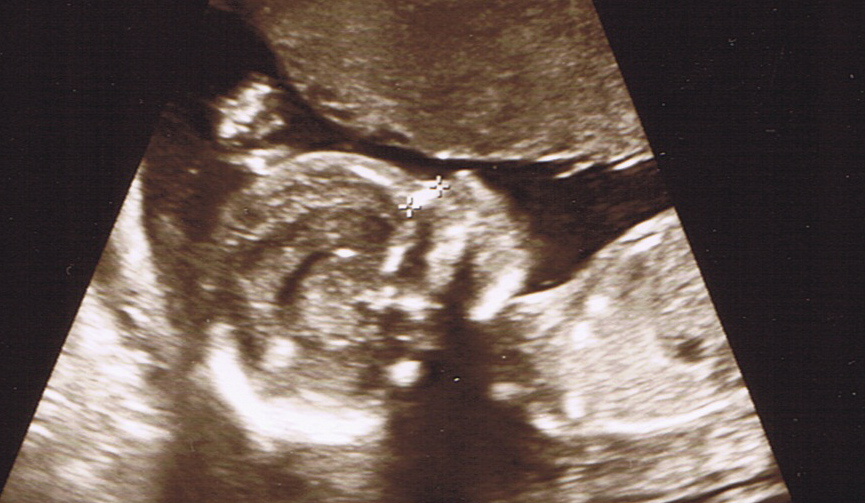

This morning Jodi and I saw the face of an angel — our angel, a tiny new Thorplet, just 11 ounces now at 18 weeks of development. Our baby pulled away from the attempts to examine his or her feet, just like all of our children, but otherwise kept uncooperatively still, making it difficult to get a good look at the tiny, chugging heart. When the sonographer was finally finished her thorough examination, she took the photo above: a tired wee child, hand above head, resting peacefully.

And of course, it was made clear yet again today when we saw that beautiful profile at the top of this post. There’s a reason that the Knights of Columbus and other Catholic and pro-life organizations are investing in ultrasound machines for clinics and teaming with expecting mothers to show live ultrasounds of their babies to middle- and high-school students. There’s no better way to recognize the humanity of others than to see them face to face.